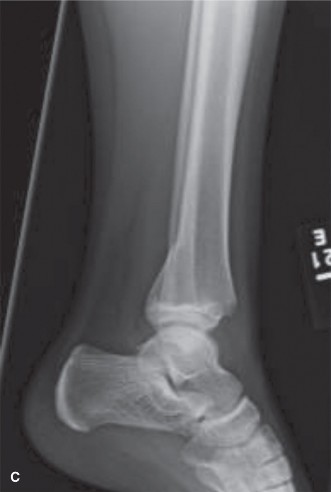

Potential for other intra-articular pathology with tibial tubercle fractures? CASE 10 You are called to the emergency room to evaluate a 13-year-old male complaining of acute right ankle pain. He reports that he injured his ankle earlier in the day when another player “took him out” during a soccer match. He was unable to bear weight through the right lower extremity and was brought promptly to the hospital for evaluation and management of his injury. An anteroposterior radiograph of the patient’s ankle is shown in Figure 10–14.

Figure 10–14

Which of the following answers correctly pairs the eponym commonly used to

The correct answer is (B). The radiograph shown demonstrates a Tillaux fracture, the eponym used to describe transitional ankle fractures in adolescents characterized by two main fragments: one fragment being the anterolateral distal tibial epiphysis and the second including the tibial metadiaphysis, the physis, and the posteromedial epiphysis. On an anteroposterior radiograph, the fracture line appears to run through the physis and exit through the epiphysis. The anatomic structure attached to this piece is the anterior inferior tibiofibular ligament (AITFL), one of the primary syndesmotic ligaments of the ankle. Chopart injuries involve the midtarsal joint. The Chaput fragment is another eponym (used more commonly in adult ankle fractures) to describe the fracture piece that remains attached to the AITFL. The anterior talofibular ligament (ATFL) is the most commonly injured structure in lateral ankle sprains.

After reviewing the patient’s radiographic imaging, you diagnose an injury involving the growth plate of the distal tibia. Which of the following answers correctly pairs the description of this injury with its associated Salter–Harris fracture classification?

The correct answer is (D). The Salter–Harris classification system for describing fractures in skeletally immature individuals is as follows: Salter–Harris I fractures involve the growth plate only and are not usually evident on plain radiographs. This is usually a clinical diagnosis. Salter–Harris II injuries involve the physis (growth plate) and then the fracture line “exits” into the metaphysis (away from the joint).

This metaphyseal fragment is often called a “Thurston–Holland” fragment. Salter–Harris III injuries involve the physis and then the fracture exits into the epiphysis (towards the joint). The injury depicted in Figure 10–14 is a Salter–Harris III. Salter–Harris IV injuries involve the growth plate, with extension of the fracture into both the epiphysis and metaphysis. Salter–Harris V injuries are crush injuries through the growth plate that are often radiographically indistinguishable from Salter–Harris I injuries initially, but have higher rates of physeal arrest due to the increased force that produces this injury.